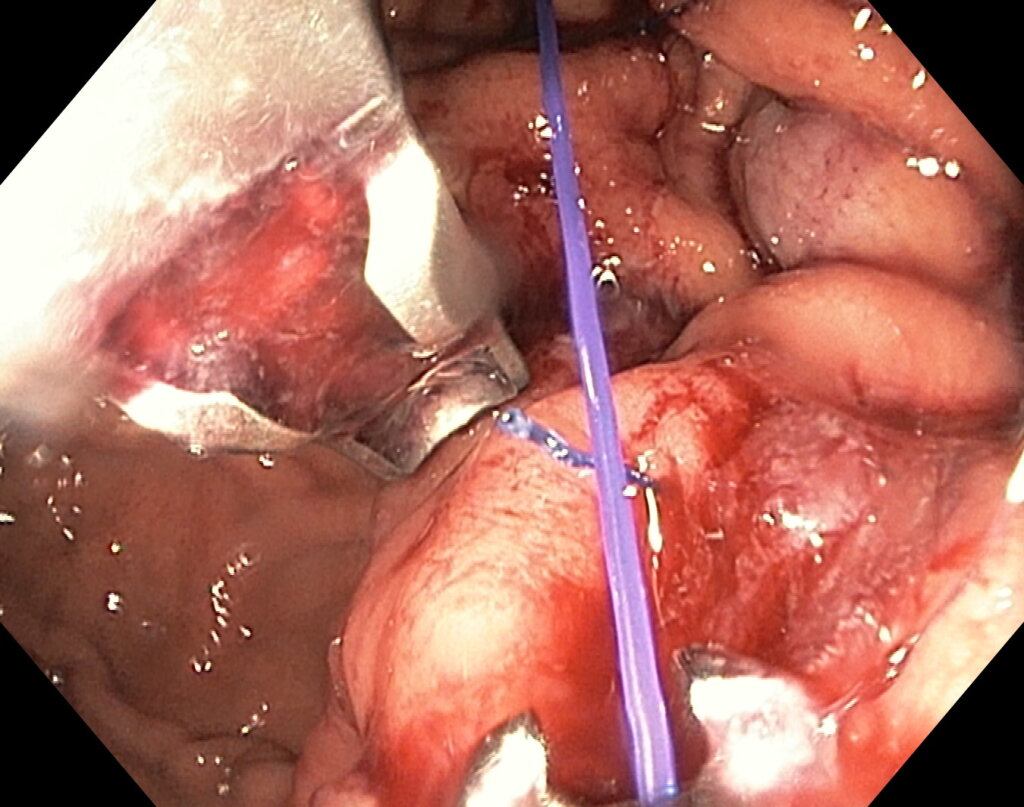

Комбинированный метод представляет собой эндолюминальное ушивание желудка (формирование «рукава») с добавлением локальной аргоноплазменной коагуляции (АПК, APC — поверхностная неконтактная термальная абляция слизистой) в зоне свода желудка с целью индуцирования контролируемого фиброза и снижения секреции грелина. ESG выполняется перорально под визуальным контролем с использованием системы Overstitch;

После предварительного обследования произведена операция: ESG + АПК (APC) свода; всего использовано 6 швов, время процедуры ≈ 120 минут.

Под видеоконтролем выполнена эндоскопическая рукавная гастропластика: сшивание стенок желудка при помощи аппарата Overstitch Boston Scientific по длине тела с целью уменьшения объёмов съедаемой пищи.